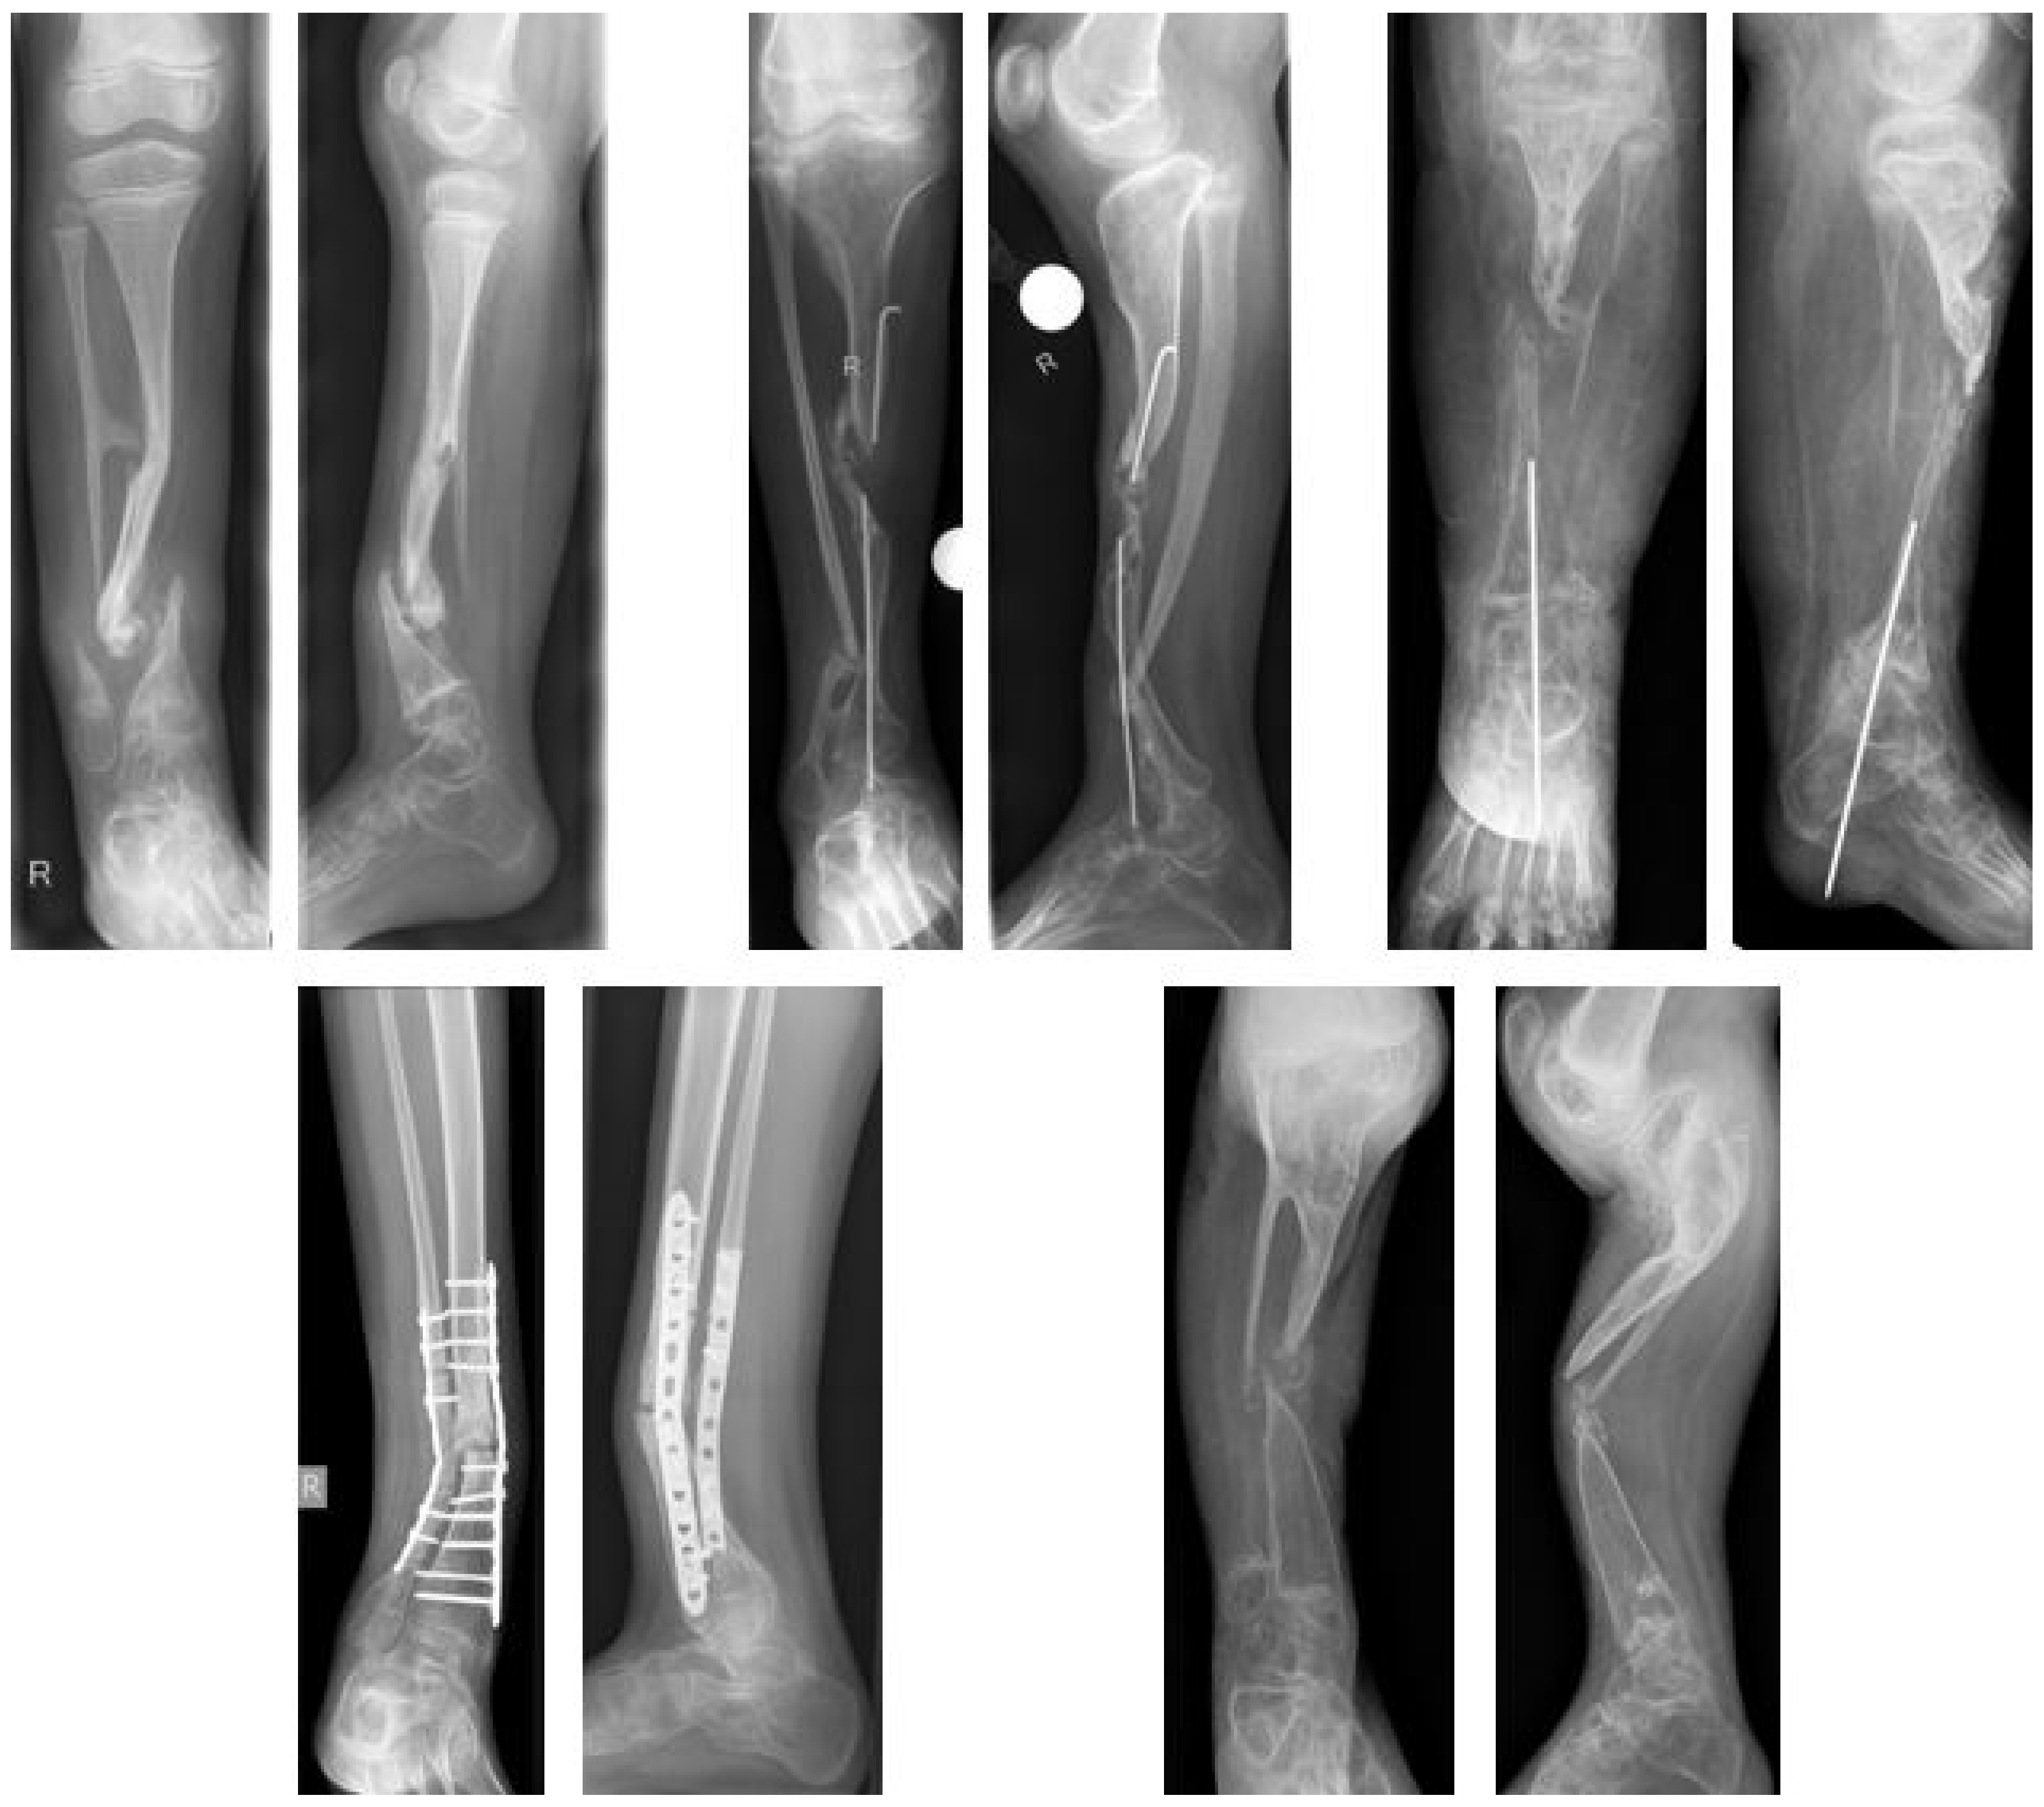

In 29 of 69 patients with CPT (42%) an association with NF type 1 was observed. In the study cohort, NF type I was present in 12 of 26 patients (46%). Even though, the true prevalence might have been higher, as a molecular genetic analysis was not initiated in all patients. There were 16 females (62%) and ten males (39%). More than two thirds of patients included (69%) had undergone previous surgeries with a mean of 2.6 (1–7) interventions, mostly performed in external institutions (Figure 4). The mean age at first surgical intervention at the study center was 8.7 (2.8–14.9) years; only one child included in the study was younger than three years. Eight patients (31%) had not received previous surgical treatment; these patients had a mean age of 6.5 (2.8–11.0) years at the time of the index procedure.

Figure 4. Examples of previous failed surgeries (a.p. and lateral views).